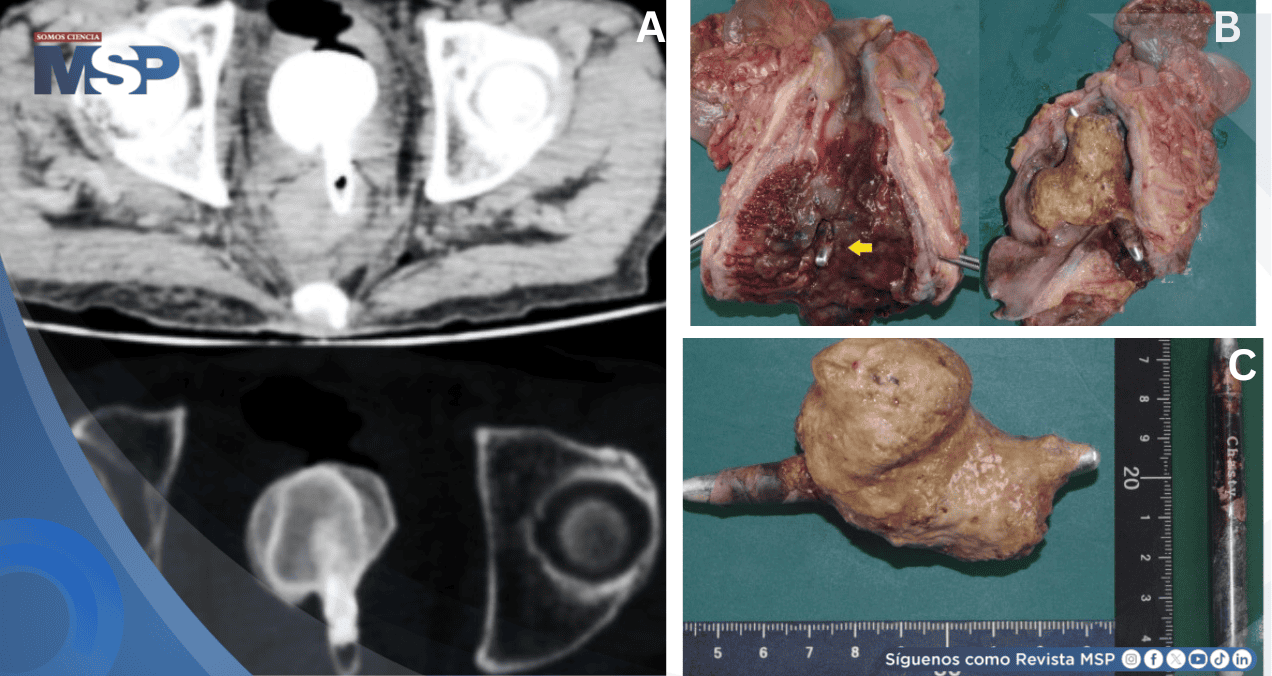

La autopsia reveló un cálculo vesical gigante de 6,5 cm adherido a un delineador de ojos que había penetrado desde el recto hacia la vejiga, causando pielonefritis y sepsis fatal.